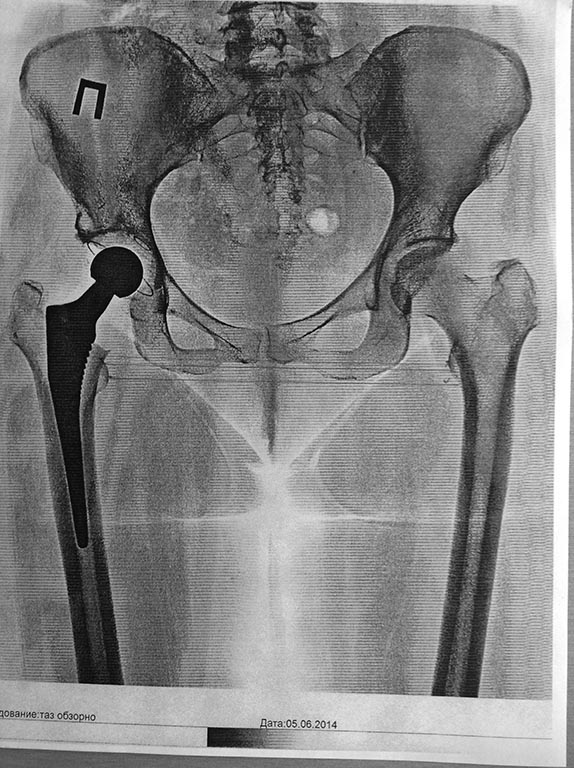

Больной по поводу диспластического коксартроза выполнено тотальное эндопотезирование правого тазобедренного сустава, использованы минимальные размеры ножки эндопротеза и головки

относительное удлинение конечности составляет 2см, по заявлению больной 3,5см. абсолютное удлинение по данным контрольной рентгенограммы составило 11мм. Операция выполнена по платным медицинским услугам.Больная угрожая судебным иском требует возврата денег за эндопротез и лечение с компенсацией морального вреда. Хочу услышать мнение коллег.

PS на мой взгляд, здесь больше 1,1 см (варусные шейки), но это другая история.

Здравствуйте коллеги! Представленный случай протезирования выполнен на отлично!!!

на отлично? если я получаю такую картинку (что бывает), то считаю это своим "косяком"